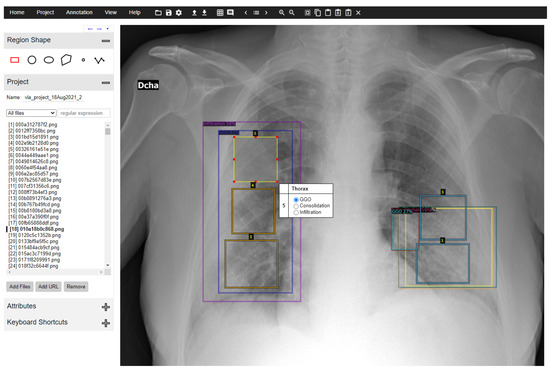

- Dutta, A.; Zisserman, A. The VIA Annotation Software for Images, Audio and Video. In Proceedings of the MM’19, 27th ACM International Conference on Multimedia, Nice, France, 21–25 October 2019; ACM: New York, NY, USA, 2019. [Google Scholar] [CrossRef]

- Dutta, A.; Gupta, A.; Zissermann, A. VGG Image Annotator (VIA). Version: 2.0.10, 2016. Available online: http://www.robots.ox.ac.uk/~vgg/software/via/ (accessed on 1 March 2021).

- Code Documentation for VGG Image Annotator 2.0. Available online: https://gitlab.com/vgg/via/-/blob/via-3.x.y/via-2.x.y/CodeDoc.md#core-data-structures (accessed on 1 March 2021).